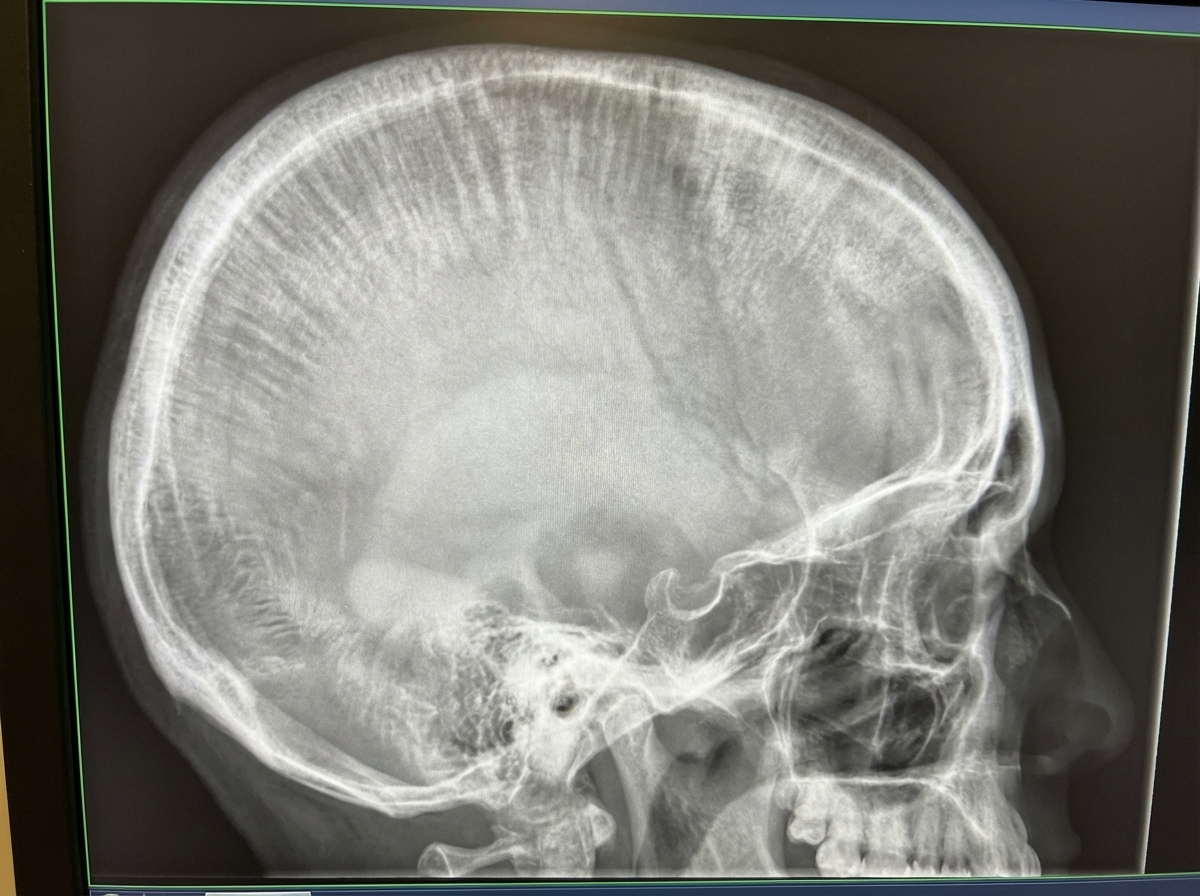

Which of the following conditions can manifest with the shown X-ray findings in the skull?

Explanation: ***Thalassemia*** - Causes **"hair-on-end"** or **"crew-cut"** appearance on skull X-ray due to **diploic widening** from compensatory **extramedullary hematopoiesis**. - The chronic hemolytic anemia leads to **bone marrow expansion** and characteristic **perpendicular trabeculae** extending outward from the skull. *Acute Myeloid Leukemia* - Primarily causes **lytic bone lesions** and **osteopenia** rather than the specific hair-on-end pattern. - X-ray findings typically show **punched-out lesions** and **pathological fractures**, not diploic expansion. *Iron deficiency anemia* - Does not cause significant **bone marrow expansion** as it's primarily a **microcytic hypochromic** anemia. - X-ray findings are typically **normal** or may show **osteopenia** but never the hair-on-end appearance. *Megaloblastic Anemia* - Results from **vitamin B12** or **folate deficiency** causing **ineffective erythropoiesis**. - Does not produce the **compensatory extramedullary hematopoiesis** necessary for diploic widening and hair-on-end pattern.